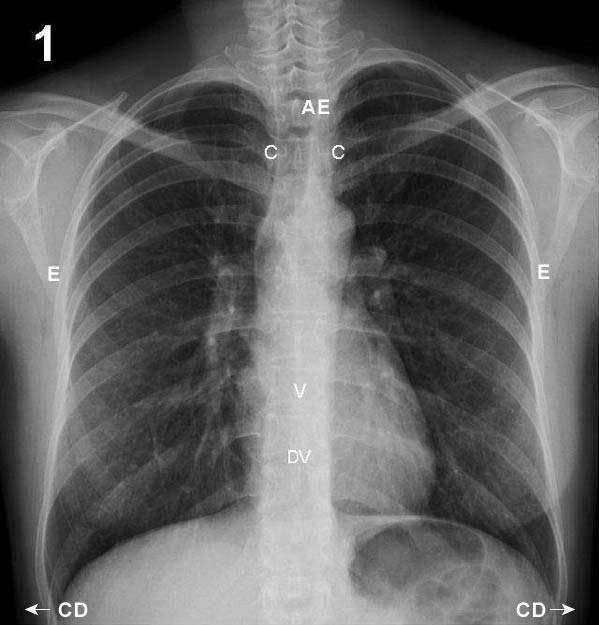

Esta es una radiografía frontal o póstero-anterior (PA) de buena calidad, de un sujeto normal en posición de pies.

Para que una radiografía de tórax se considere adecuada debe reunir las siguientes características que Ud. debe identificar en la placa:

a) La placa debe incluir la totalidad del tórax, desde los vértices pulmonares hasta el fondo de los recesos costodiafragmáticos (CD) tanto en proyección frontal como lateral. Las escápulas (E) deben estar desplazadas fuera de los campos pulmonares.

b) La radiografía frontal debe estar bien centrada, lo que se puede verificar comprobando que los extremos esternales de ambas clavículas (C) equidisten de la sombra central de las apófisis espinosas vertebrales (AE).

c) La dureza o penetración de los rayos debe ser tal que alcance a distinguirse detrás de la sombra cardíaca la columna vertebral tenuemente segmentada en cuerpos vertebrales (V) y discos intervertebrales (D). Debe existir, además, una gama bien diferenciable de grises, negro y blanco.

d) Salvo que se haya solicitado de otra manera, la placa se toma en inspiración profunda sostenida. El tamaño, posición y forma de las estructuras endotorácicas varía considerablemente en espiración y, si no se han detenido los movimientos respiratorios, las imágenes, especialmente de los vasos, resultan borrosas.

e) Si lo permite el estado del paciente, la radiografía de tórax se toma ordinariamente en posición de pies. Esto determina una morfología y topografía características debidas a la acción craneo-caudal de la fuerza de gravedad. Un índice de que la radiografía ha sido tomada en esta posición es la presencia de la burbuja de aire del estómago (G) en contacto con la cara inferior del hemidiafragma izquierdo.